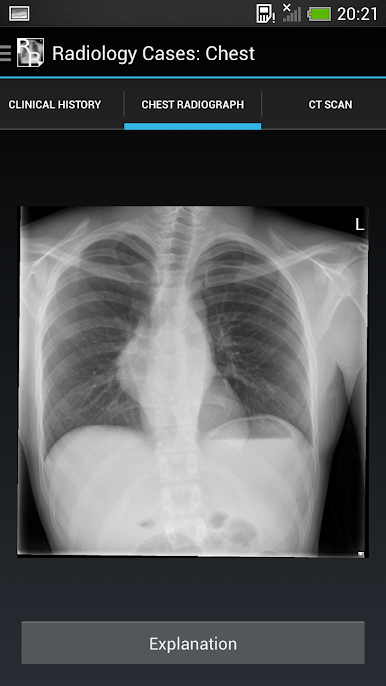

It consists of 26 cases, each with a brief history and a chest x-ray. The user should try to interpret each chest x-ray before revealing the explanations at the bottom of each page.

The aim is to gain an understanding of the basic principles of chest x-ray interpretation and specific radiographic features of common diseases. The diseases encountered are discussed along the way and many of the cases have a scrollable

CT to help with understanding the chest x-ray appearances.